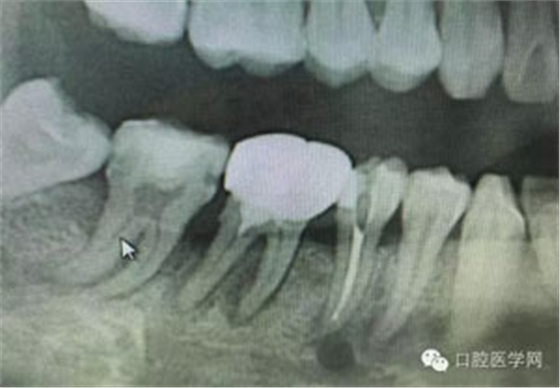

病例1:患者迫切希望保留自己的這一顆牙齒,根尖周陰影比較大,二度松動(dòng).而且旁邊有種植修復(fù)體,和患者溝通好后,治療好后觀察一個(gè)月后冠修復(fù),因?yàn)橛蟹N植的后期修復(fù),所以有了機(jī)會(huì)觀察,術(shù)后三個(gè)月和術(shù)后四個(gè)月,根尖恢復(fù)的還算不錯(cuò),希望能夠繼續(xù)觀察下去.這樣子的病例,做的時(shí)候我們一定要非常的小心,和患者要有充分的溝通以及不同科室的溝通然后決定怎么樣做比較好,假如就是出現(xiàn)了問(wèn)題,到時(shí)候我們也比較好處理些,免得我們自己到時(shí)候不好收?qǐng)觥?/span> 病例2:364647中齲的樹(shù)脂充填,現(xiàn)在樹(shù)脂的充填材料非常之多,有些時(shí)候,我們感覺(jué)有了好的材料我們就可以做出好的修復(fù),可是這是在我們有扎實(shí)的基本功的基礎(chǔ)上的,我們可以沒(méi)有那么好的樹(shù)脂,那么多的顏色選擇,修復(fù)的那么的逼真,但是我們至少要恢復(fù)患者牙齒的功能,將腐質(zhì)去除干凈,薄壁弱尖消除掉,選擇好適應(yīng)癥,給患者以盡可能好的修復(fù)。 來(lái)源于KQ88